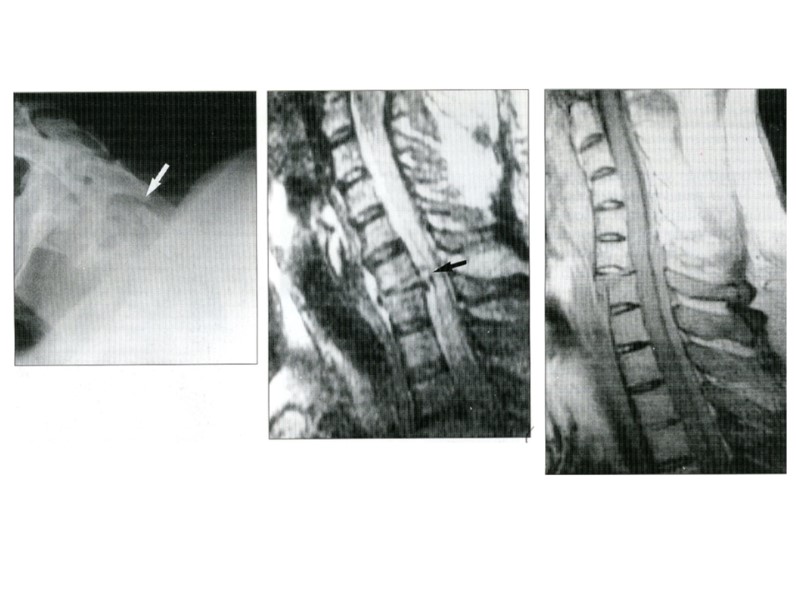

Pacienta N.,44 ani suferă de LES. În rînd cu alte simptoame au apărut dureri în articulaţiile coxomefurale pe dreapta. A – Radiografia articulaţiilor coxofemurale –fără modificări patologice. B – Scintigrafia: pe dreapta cumulare intensivă a farmaceuticului

-A Explorare radiologică:suspiciune de NA pe stînga -B T1 suspendată IMR frontală articulaţiei coxomemurală pe stînga. Se constată intensitate superioară în regiunea osteonecrozei, ce manifestă prezenţa degeneraţiei adipoase.

Explorare IRM a mîinii drepte. A-B – sînt efectuate în incidenţa coronariană T1 Imaginea C efectuate în incidenţa transversală T1. se constată sinovita de gr III. Tomografia prin IRM a permis diagnosticul diferenţiat între AR şi artrita reactivă prin constatarea sinovitei hipertrofice ce este caracteristic pentru AR.